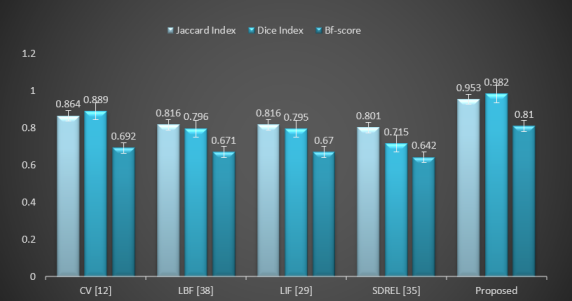

IV-E Evaluation Measurements

Furthermore, the accuracy of the segmentation results can be assessed quantitatively using an image segmentation evaluation measurement. The most frequently used segmentation evaluation techniques are the Dice Index, Jaccard similarity index (Jaccard index), and contour matching score (bfscore). The same system and data are used to measure these evaluations for all models discussed above.

The Dice Index, often referred as an overlap index, is calculated by overlapping the segmentation mask and the ground truth mask. The value of the Dice Index indicates by how much the segmentation result is equivalent to the actual result. The range of the Dice Index is between [0, 1], where a value closer to 1 shows a more accurate segmentation. The dice Index is calculated using the segmentation result (SR) and ground truth (GT). The formula used to calculate the Dice Index is as follows:

| (31) |

where and describe the segmented results and the actual ground truth, respectively.

After applying the Dice Index, we use the Jaccard Index, the second most frequently used image segmentation evaluation technique. The range and behavior of its value is same as that of the Dice Index. The Jaccard Index is calculated by the following:

| (32) |

Similarly, the contour matching score (e.g., the BF score) measures how close the boundary of the segmented regions matches the ground truth boundary and is calculated through the following:

| (33) |

where is the ratio of the number of points on the boundary of the SRs that are sufficiently close to the boundary of the GT to the length of the boundary SR, and is the ratio of the number of points on the boundary of the GT that are sufficiently close to the boundary of the SRs to the length of the GT boundary. The range of the BF score is in [0,1]. The higher the BF score, the better the segmentation quality.

These quantitative comparisons of all models were conducted to measure the Dice Index, Jaccard Index, and BF score over the [48] dataset of dermoscopic images. Three evaluation measurements are calculated for each image shown in (13) against each model. Fig. (14) shows the mean of these evaluation measurements in a graphical context. All image segmentation evaluation analysis techniques prove that the proposed saliency driven active contour model achieves the highest Dice Index, Jaccard Index, and contour matching score (BFscore) in comparison to the previous related models.